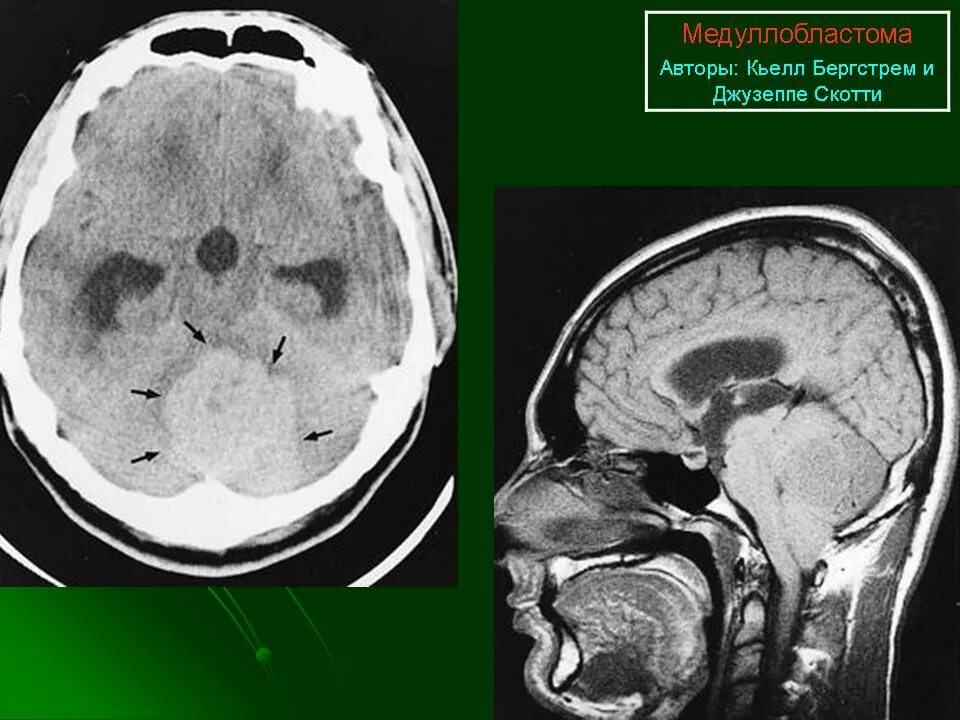

Медуллобластома это